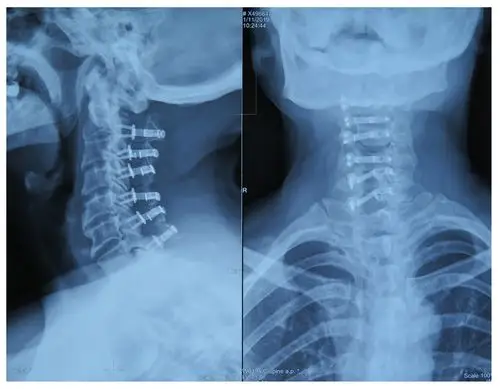

颈椎x线片,颈部x线片

颈椎x线片或颈椎ap和侧位片诊断椎间盘突出.

第一次术后,颈椎x线(颈2-7节段)